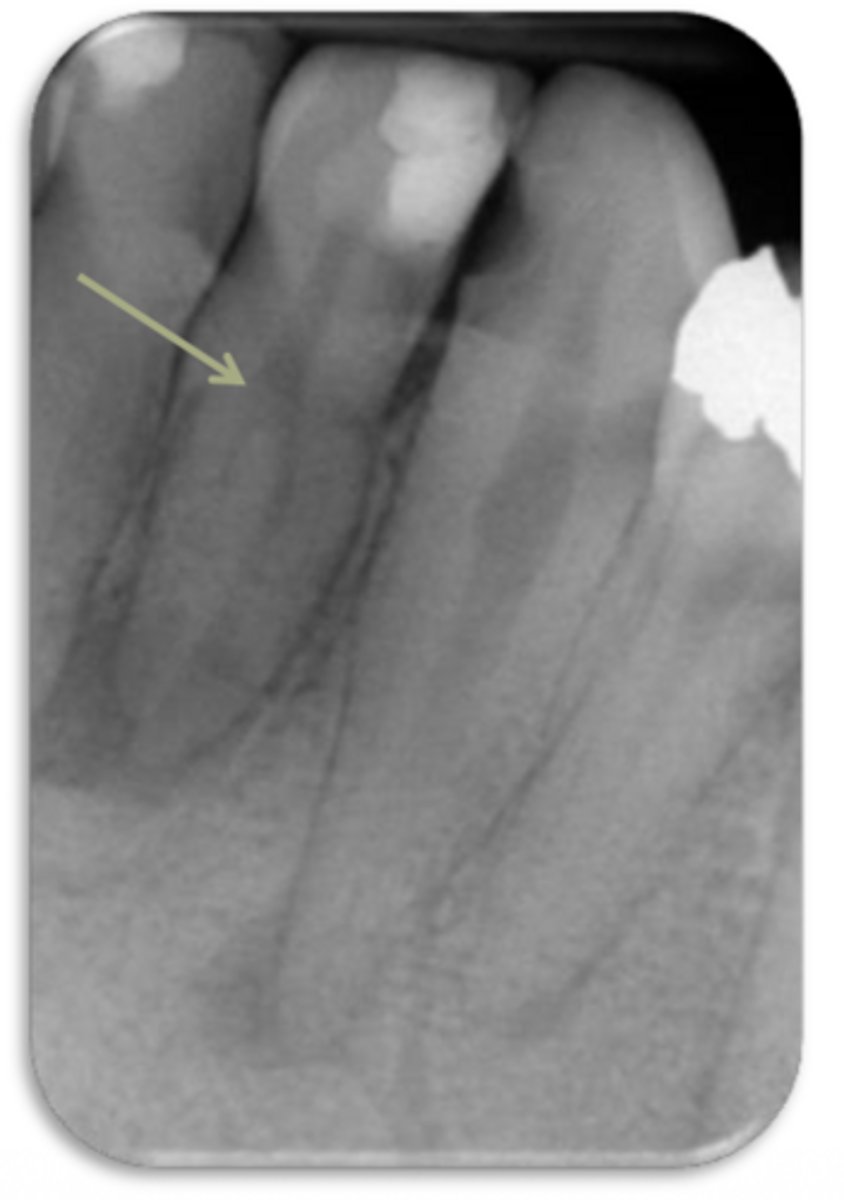

ID the problem:

external resorption